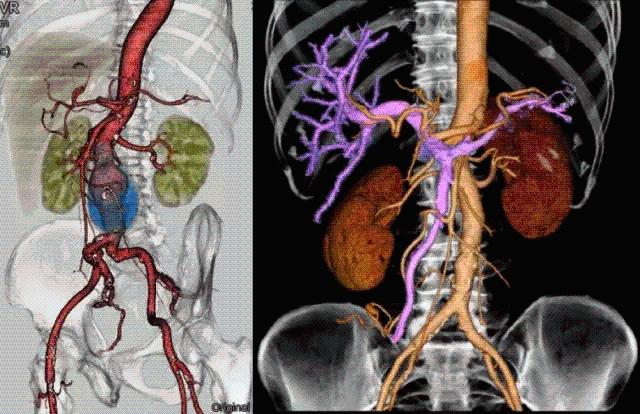

High-quality and fast 3D reconstruction and 3D rendering

Performs 3D reconstruction and volume rendering.

Side-by-side comparative assessment for pre- and post-operative scans.